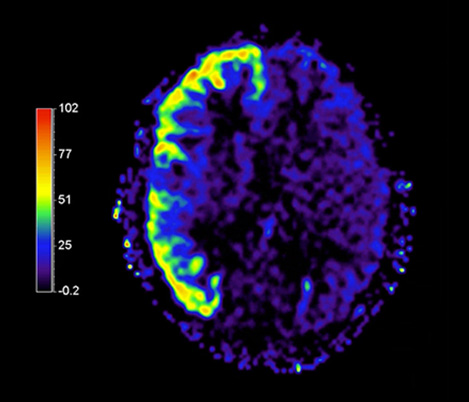

2 Definitive is defined as features that are expected to deliver alternative contrasts, functional or quantitative images

APT** and REACT**: The next steps towards non-invasive imaging strategies for pediatric MRI

Jeffrey H. Miller, MD

Vice Chair of Radiology for Research and Academic Affairs, Phoenix Children’s Hospital, Phoenix, AZ, USA